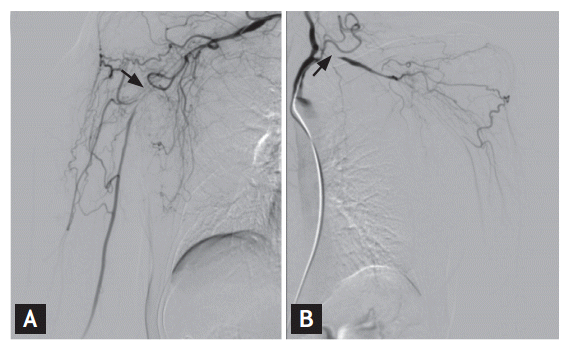

Cervical spine magnetic resonance imaging showed that both cord compression and stenosis were absent, but upper extremity angiography revealed severe stenosis of both the subclavian and axillary arteries (Fig. 1). Arteries distal to the site of stenosis, including the brachial, radial, and ulnar arteries, exhibited decreased blood flow, with the development of collateral arteries in the surrounding region. CT aortography revealed uptake by the walls of both the thoracic and abdominal aortas, suggestive of a large-vessel vasculitis such as TA. A pulmonary embolism was also accidentally found. FDG-PET/CT was performed after injection of 12.1 mCi 18F-FDG to assess the vasculitis. Linear distinct FDG uptake was evident in both the subclavian and axillary arteries (maxSUV, 2.2), and the ascending aorta and aortic arch (maxSUV, 2.1), indicating vasculitis (Fig. 2). We found no evidence of malignancy. Although she denied any symptom of dyspnea, a pulmonary embolism was found by chance. CT revealed multiple embolisms of both pulmonary arteries (Fig. 3). The anti-cardiolipin antibody immunoglobulin M (IgM) titer was 14.10 IgM phospholipid (MPL) units (normal range, < 7.0). The anti-β2 glycoprotein-1 antibody IgM titer was 22.0 U/mL (normal range, < 5), and the anti-lupus anticoagulant antibody titer was 1.91 (normal range, 0 to 1.24). The level of protein S was 54.5% (normal range, 50.8 to 116.9), the level of protein C was 173% (normal range, 70 to 148), and the level of antithrombin III was 120% (normal range, 65 to 129). On follow-up blood tests run 12 weeks later, she was positive for anti-cardiolipin antibody IgM, at 11.80 MPL units (normal range, < 7.0).

Figure 1.

Arteriography of both upper extremities. Severe stenosis is evident in the right subclavian and axillary arteries (A, arrow), and in the left subclavian artery, with reduced blood flow distal to the lesion (B, arrow).